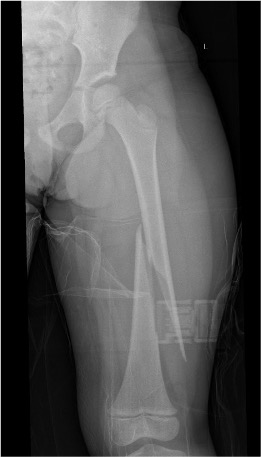

Subtrochanteric fractures

Issues

Non operative treatment rarely indicated in older children as acceptable alignment hard to maintain

Options

Plate v TENS

- no difference in outcome between plate and TENS

- plate patients tended to be older and heavier

Li et al J Pediatr Orthop B 2013

- 54 children aged 5 - 12 with subtrochanteric fractures

- better outcomes and lower complication rate with plate compared to TENS